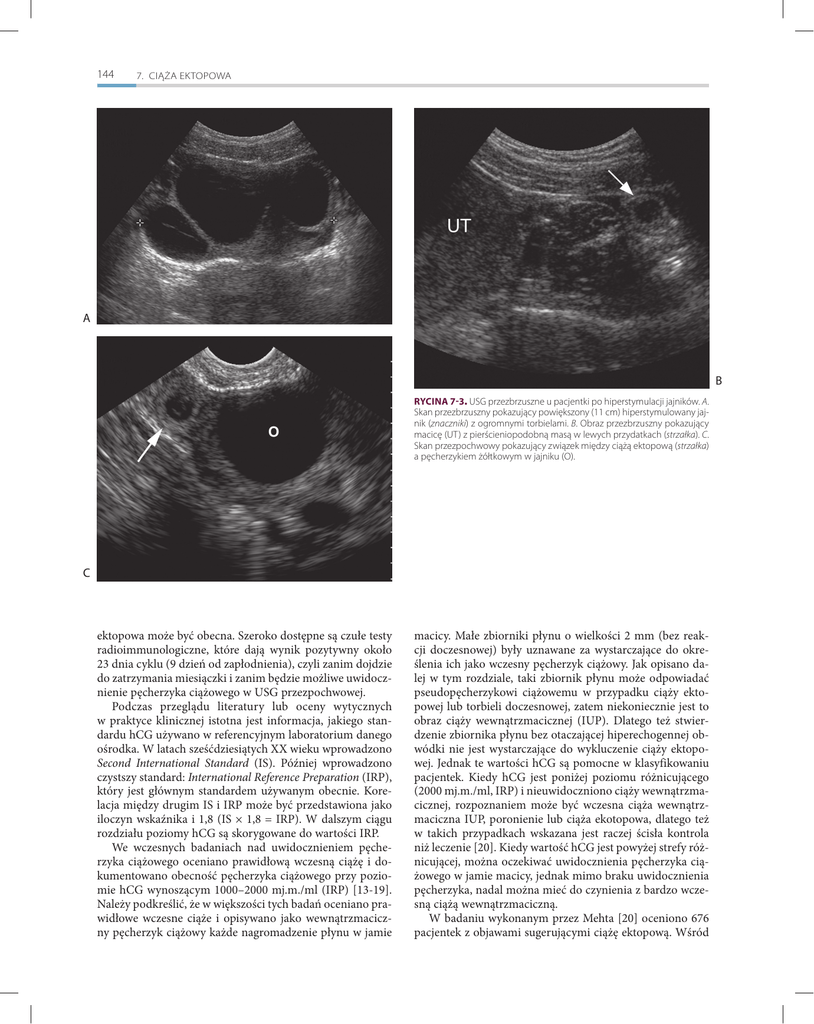

RYCINA 7-3. USG przezbrzuszne u pacjentki po hiperstymulacji jajników. A.

Skan przezbrzuszny pokazujący powiększony (11 cm) hiperstymulowany jajnik (znaczniki) z ogromnymi torbielami. B. Obraz przezbrzuszny pokazujący

macicę (UT) z pierścieniopodobną masą w lewych przydatkach (strzałka). C.